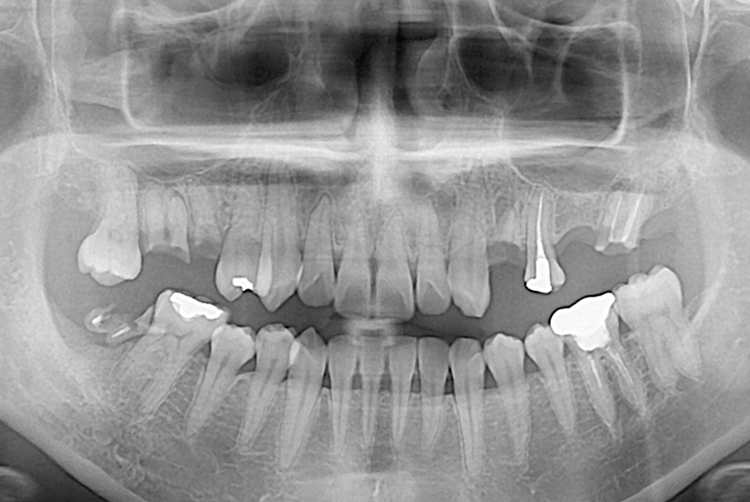

[임플란트] 임플란트

치료후 : 2018-08-23

세종치과는 많은 환자와 다양한 케이스를 바탕으로 항상 편안한 임플란트 수술을 제공하고자 노력하고,

오래동안 튼튼히 쓸 수 있는 임플란트 수술을 가장 큰 목표로 삼고 있습니다